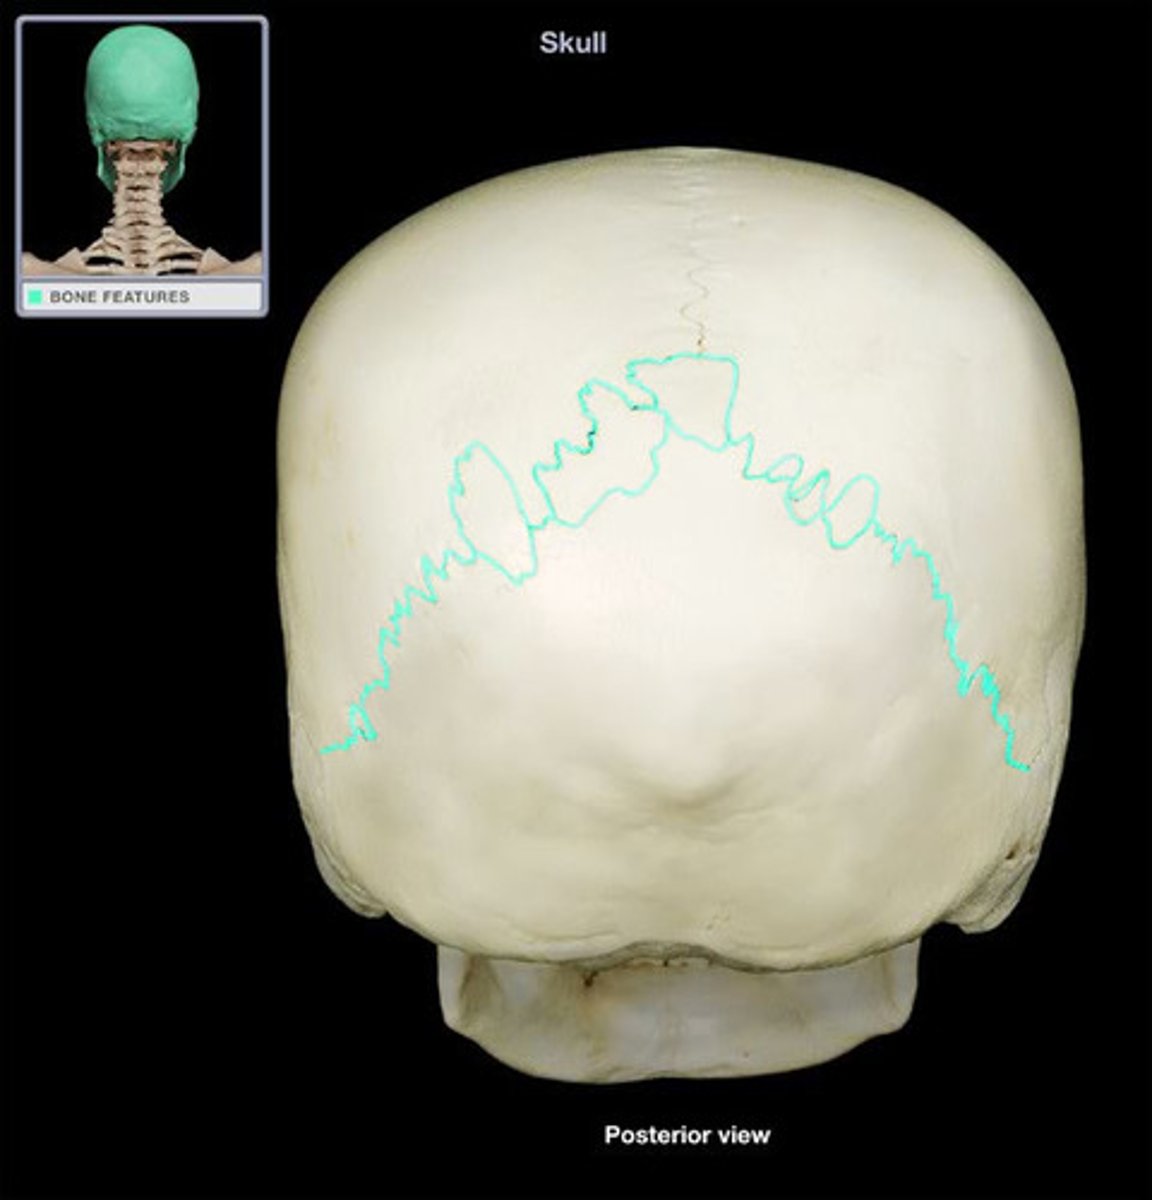

coronal suture

sagittal suture

lambdoid suture

squamous suture

suture

interlocking line of union between bones